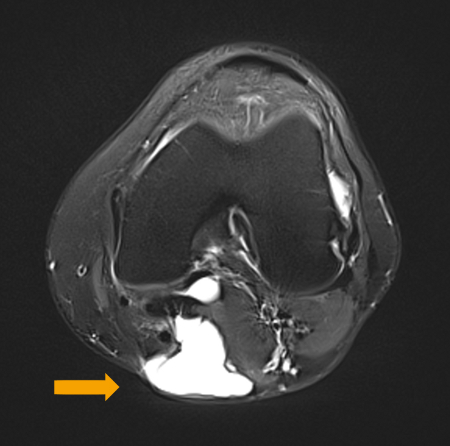

A ruptured haemorrhagic popliteal cyst extending in the calf

Stony Brook University Medical Center private collection; used with permission

Preoperative T2-weighted MRI showing posterior fluid collection communicating with posterior medial joint in a patient with a popliteal cyst secondary to pigmented villonodular synovitis

Adapted from Tosti R, Kelly JD 4th. Pigmented villonodular synovitis presenting as a Baker cyst. Am J Orthop (Belle Mead NJ). 2011;40:528-531; used with permission